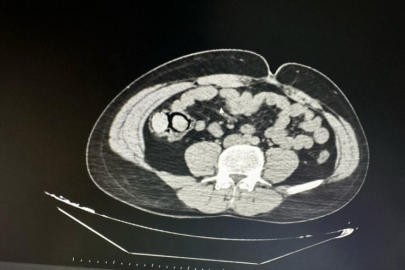

Bingöl Emniyet Müdürlüğü Narkotik Suçlarla Mücadele Şube Müdürlüğüne bağlı narko-timleri akıllara durgunluk veren bir uyuşturucu kaçakçılığını çözdü. Ekiplerin çalışmaları neticesinde otobüs ile Bingöl'e gelen şüpheli yabancı uyruklu 2 şahsın iç beden muayenesinde 10 parça halinde 113 gram metamfetamin maddesi tespit edildi. Emniyetteki işlemlerinin ardından mahkemeye çıkarılan 2 şahıs, uyuşturucu madde ticareti yapmak suçundan tutuklanarak Elazığ Kapalı ceza infaz kurumuna teslim edildi.